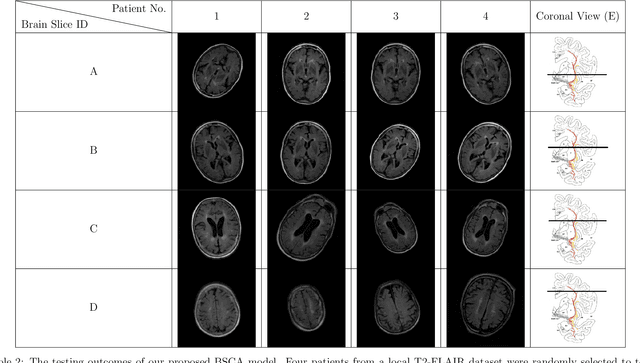

Abstract:The Cholinergic Pathways Hyperintensities Scale (CHIPS) is a visual rating scale used to assess the extent of cholinergic white matter hyperintensities in T2-FLAIR images, serving as an indicator of dementia severity. However, the manual selection of four specific slices for rating throughout the entire brain is a time-consuming process. Our goal was to develop a deep learning-based model capable of automatically identifying the four slices relevant to CHIPS. To achieve this, we trained a 4-class slice classification model (BSCA) using the ADNI T2-FLAIR dataset (N=150) with the assistance of ResNet. Subsequently, we tested the model's performance on a local dataset (N=30). The results demonstrated the efficacy of our model, with an accuracy of 99.82% and an F1-score of 99.83%. This achievement highlights the potential impact of BSCA as an automatic screening tool, streamlining the selection of four specific T2-FLAIR slices that encompass white matter landmarks along the cholinergic pathways. Clinicians can leverage this tool to assess the risk of clinical dementia development efficiently.